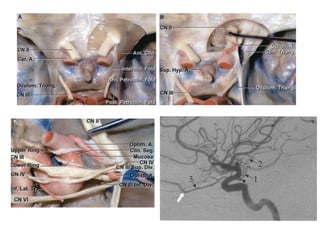

O Triângulo Opticocarotídeo

Artéria cerebral posterior

• A ACP origina-se da bifurcação da basilar unindo-se à

AComP na margem lateral da cisterna interpenducular.

Envolve o tronco encefálico em seu trajeto pelas

cisternas crural e amaines e se dirige para a porção

posterior dos hemisférios cerebrais.

• Irriga tálamo, mesencéfalo, plexo coróide, paredes do

VL e III ventrículo.

• Do ponto de vista embriológico a ACP nasce como

ramo da ACI.

Segmentação da ACP

• P1(pré-comunicante): estende-se da bifurcação da AB até a

junção da AComP. Nos casos de padrão não fetal, P1 é mais

calibroso que a AcomP.

• Os ramos relativamente constantes de P1 são:

• Artéria talamoperfurantes, que entra no encéfalo pela

substância perfurada posterior.

• Artéria coroidea póstero-medial ( dirige para III ventrículo e VL)

• Ramo para a placa colicular.

• Ramos para o pedúnculo cerebral e segmento do mesencéfalo.

Artéria cerebral posterior •A ACP origina-se da bifurcação da basilar unindo-se à AComP na margem lateral da cisterna interpenducular. Envolve o tronco encefálico em seu trajeto pelas cisternas crural e amaines e se dirige para a porção posterior dos hemisférios cerebrais. • Irriga tálamo, mesencéfalo, plexo coróide, paredes do VL e III ventrículo. • Do ponto de vista embriológico a ACP nasce como ramo da ACI.

Segmentação da ACP •P1(pré-comunicante): estende-se da bifurcação da AB até a junção da AComP. Nos casos de padrão não fetal, P1 é mais calibroso que a AcomP. • Os ramos relativamente constantes de P1 são: • Artéria talamoperfurantes, que entra no encéfalo pela substância perfurada posterior. • Artéria coroidea póstero-medial ( dirige para III ventrículo e VL) • Ramo para a placa colicular. • Ramos para o pedúnculo cerebral e segmento do mesencéfalo.